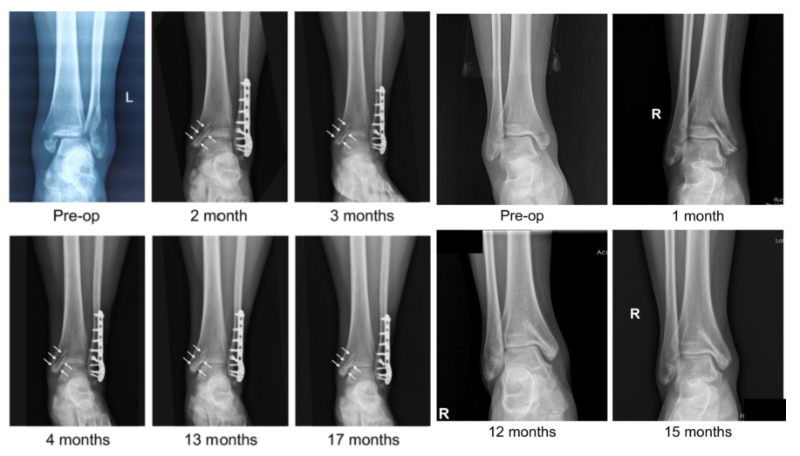

近日,國際骨科臨床轉(zhuǎn)化期刊《Journal of Orthopaedic Translation》在線發(fā)表了由上海交大戴尅戎院士、郝永強教授團(tuán)隊和丁文江院士、袁廣銀教授團(tuán)隊合作發(fā)表的可降解鎂合金骨釘1-2年的臨床試驗觀察結(jié)果,所有患者術(shù)后內(nèi)踝骨折愈合,功能恢復(fù)。研究證實了可降解鎂合金螺釘治療內(nèi)踝骨折的臨床療效及其生物安全性,為全降解鎂合金植入物等高端醫(yī)療器械進(jìn)一步的臨床推廣應(yīng)用奠定了堅實基礎(chǔ),相關(guān)成果以“Effectiveness and safety of biodegradable Mg-Nd-Zn-Zr alloy screws for the treatment of medial malleolar fractures”為題在線發(fā)表于Journal of Orthopaedic Translation,27 (2021) 96–100。這是國內(nèi)首個可降解醫(yī)用鎂合金臨床試驗的公開報道,也是國際首款含有功能涂層的可降解鎂合金骨釘?shù)呐R床試驗結(jié)果的公開報道,具有里程碑意義。

醫(yī)用鎂合金骨內(nèi)植物臨床試驗研究突破性進(jìn)展(圖1)

醫(yī)用鎂合金骨內(nèi)植物臨床試驗研究突破性進(jìn)展(圖2)